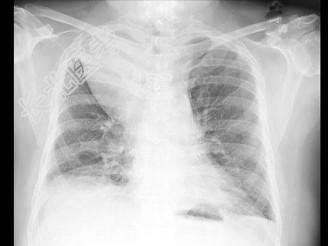

- 单项选择题男,71岁, 消瘦、咳嗽、胸痛,结合胸片和CT, 最可能的诊断是 ( )

A、脂肪肉瘤

B、心包脂肪垫

C、脂肪蓄积症

D、胸腺脂肪瘤

E、胸腺囊肿